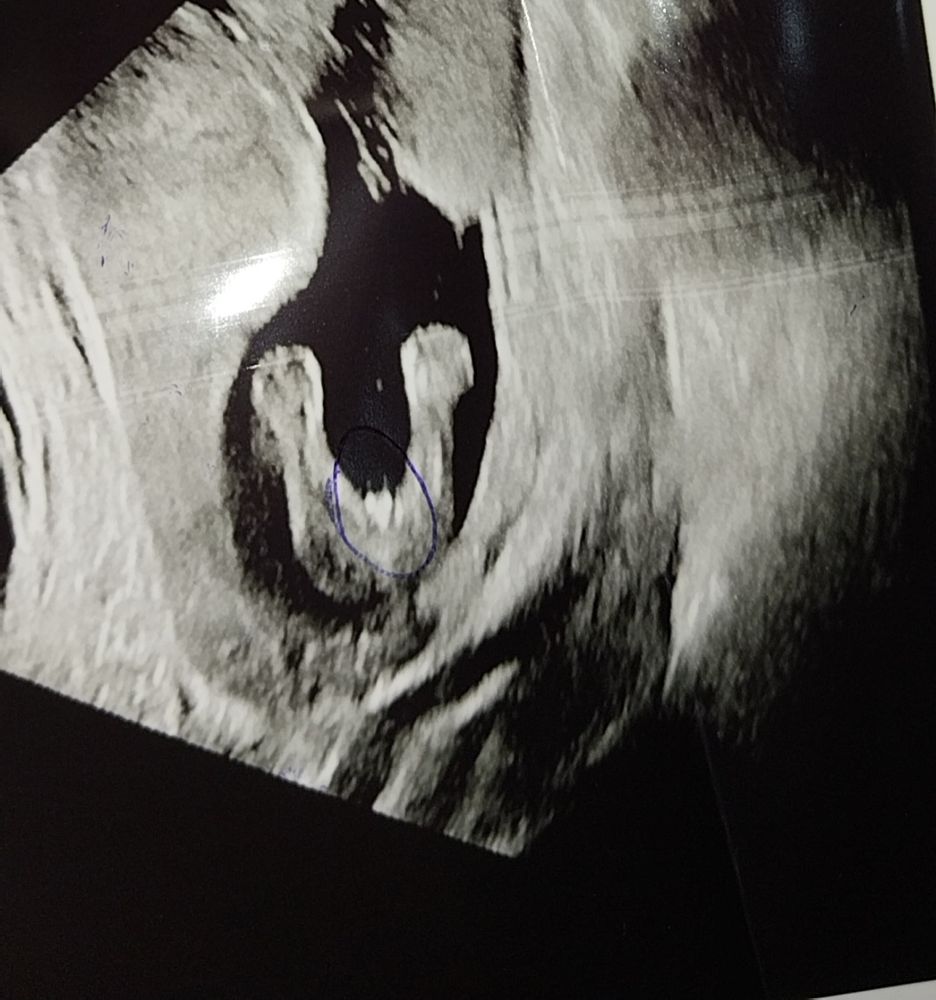

Пол малышаУ нас снова ДОЧА !!!🩷❤️🩷❤️🩷

Да не простая 😁😂я искренее не хотела знать пол до недель 30, но увидев это сердечко❤️ врач произнесла..."это чудо точно сделано с любовью, мать ты должна это видеть !!!" и повернула экран😃👀

Добро в нас

Это девочка, потом что у мальчика ещё торчит его орган по середине там где сердечко ❤️ между холмиками. Я такую картинку у себя ниразу не видела.🤭 Но, какая ж разница. Главное здоровый и доносить. 🙏